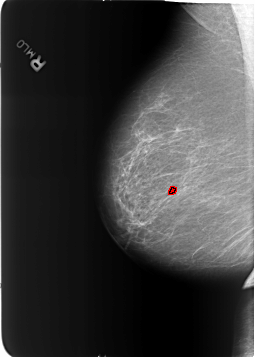

B_3211_1.RIGHT_MLO

RIGHT_MLO LINES 5712 PIXELS_PER_LINE 4080 BITS_PER_PIXEL 12 RESOLUTION 50 OVERLAY

FILE: B_3211_1.RIGHT_MLO.OVERLAY

TOTAL_ABNORMALITIES 1

ABNORMALITY 1

LESION_TYPE CALCIFICATION TYPE COARSE DISTRIBUTION N/A

ASSESSMENT 2

SUBTLETY 5

PATHOLOGY BENIGN_WITHOUT_CALLBACK

TOTAL_OUTLINES 1

BOUNDARY